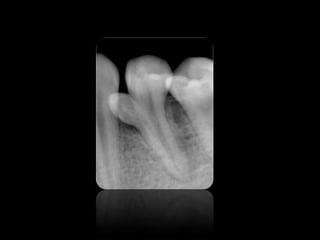

ABSCESO PERIAPICAL